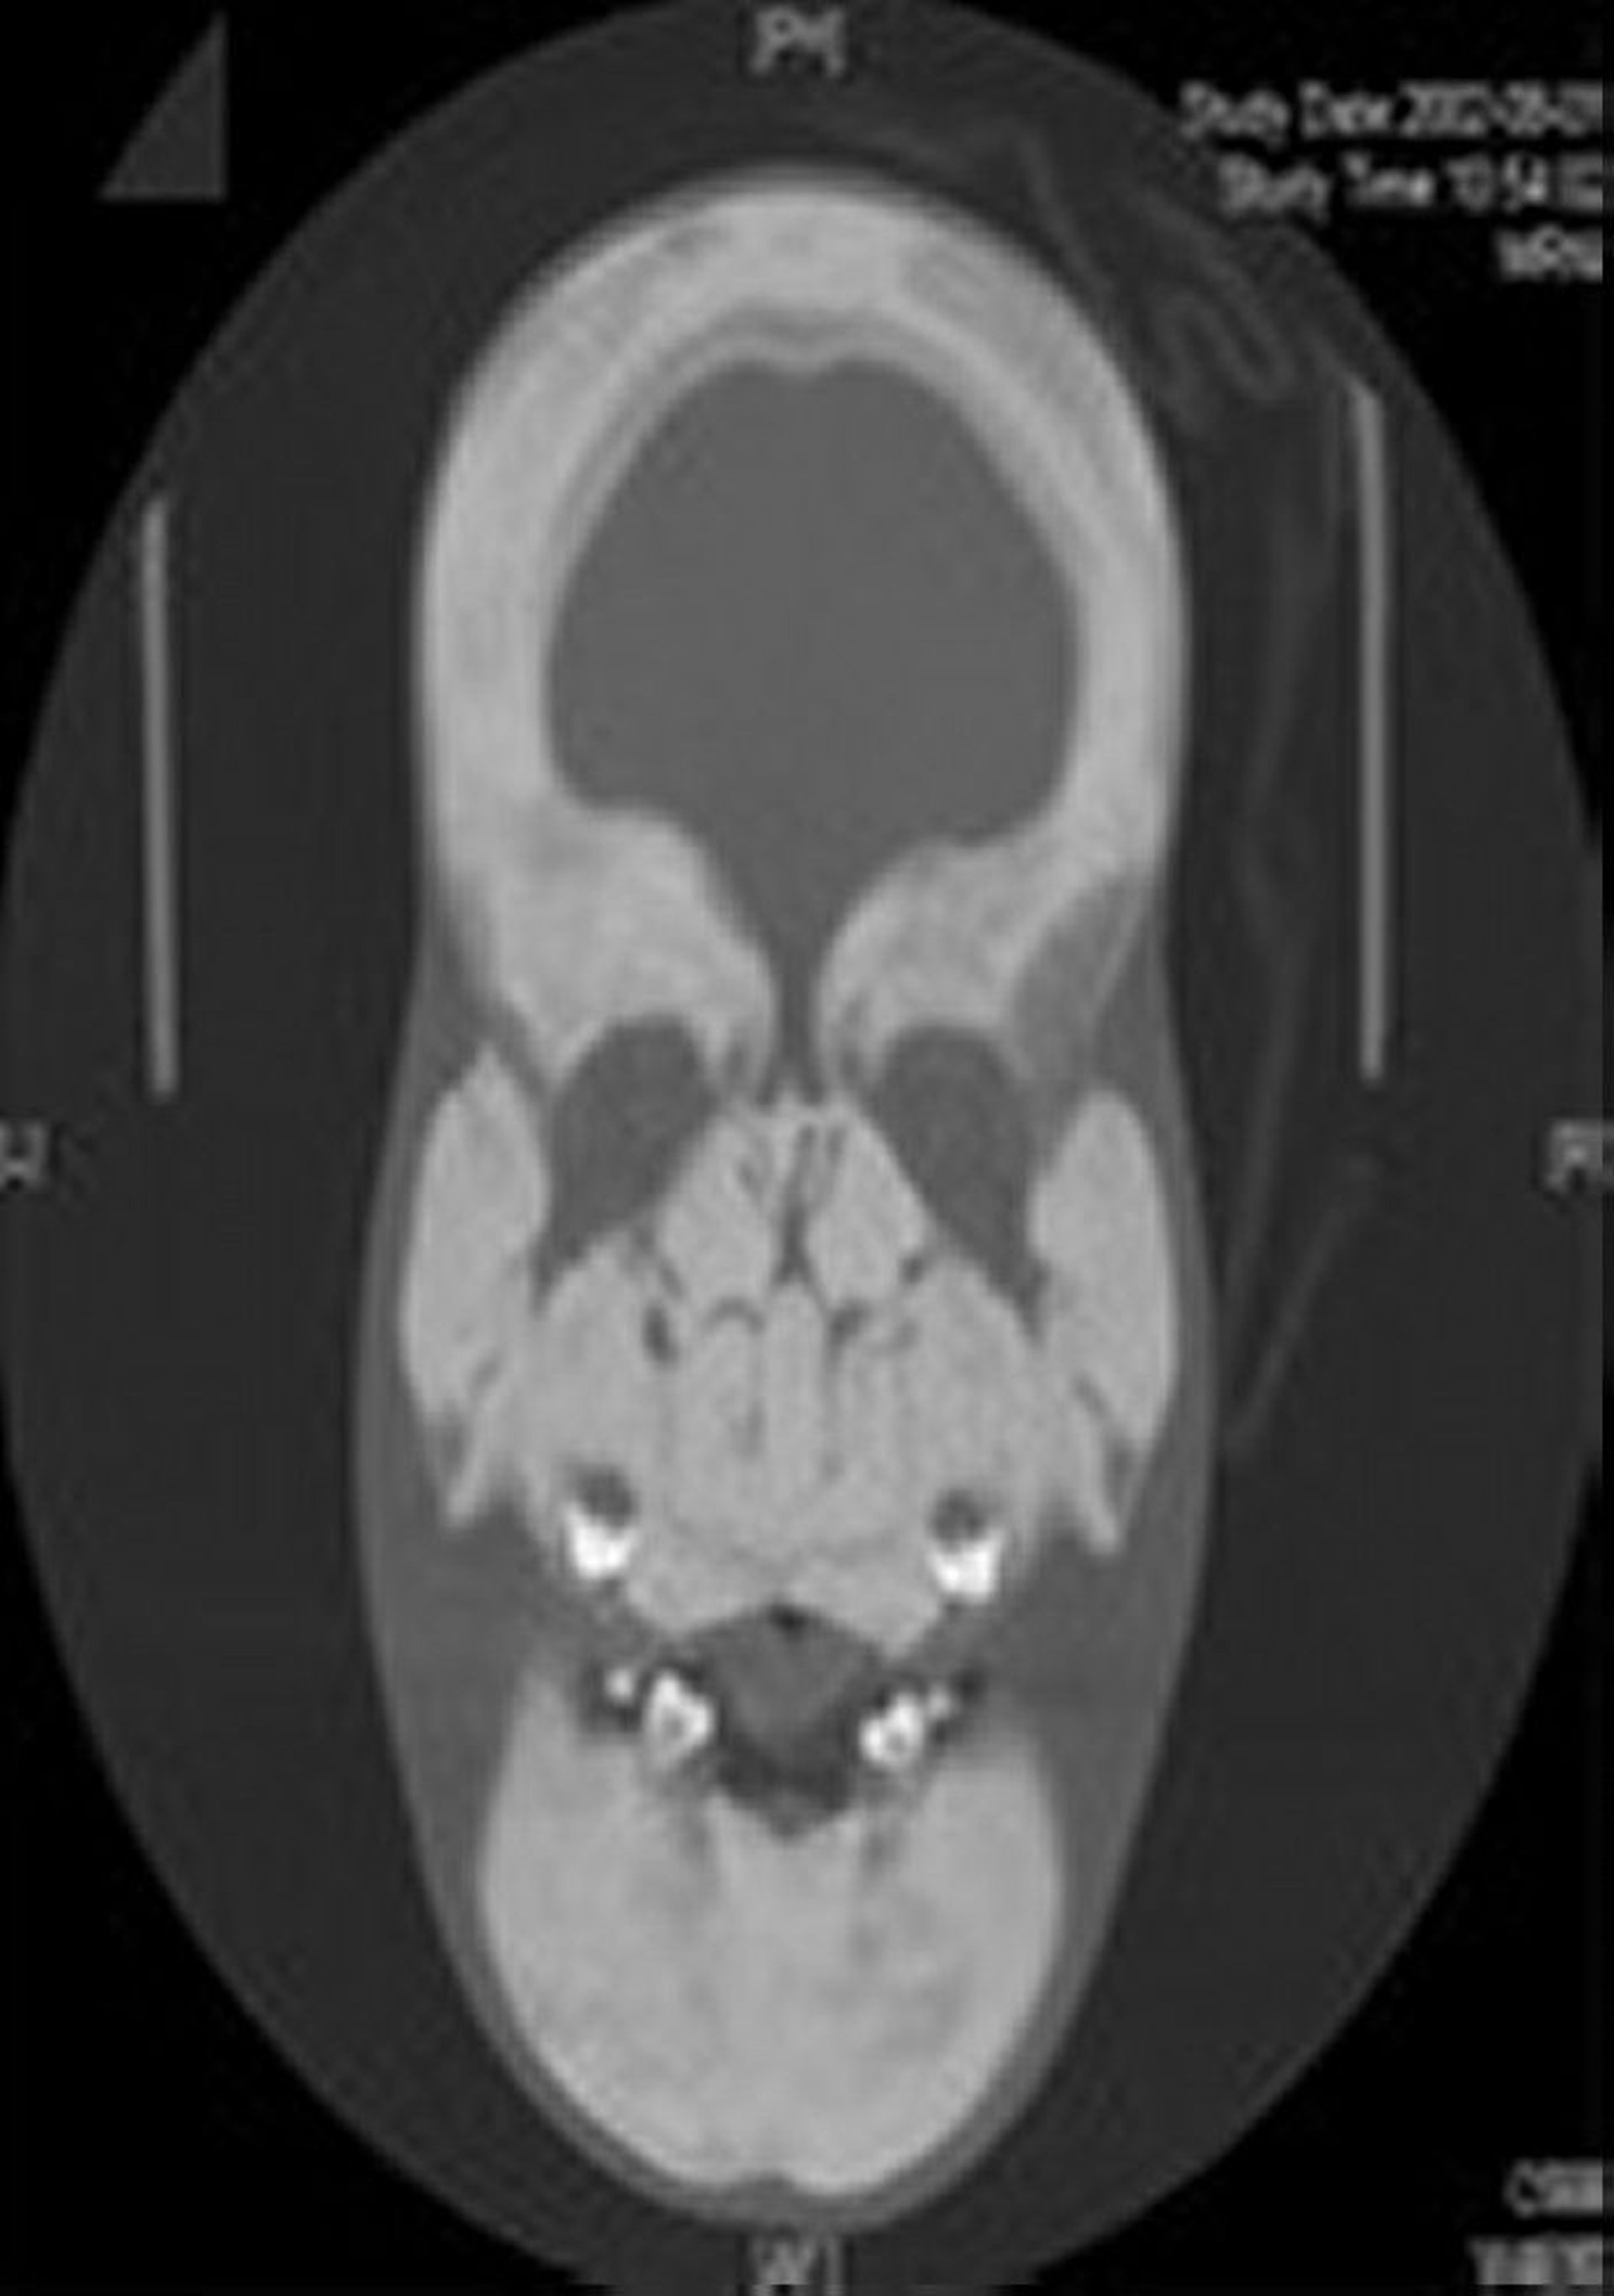

This radiograph shows marked thickening and sclerosis of the skull and whole facial bones.